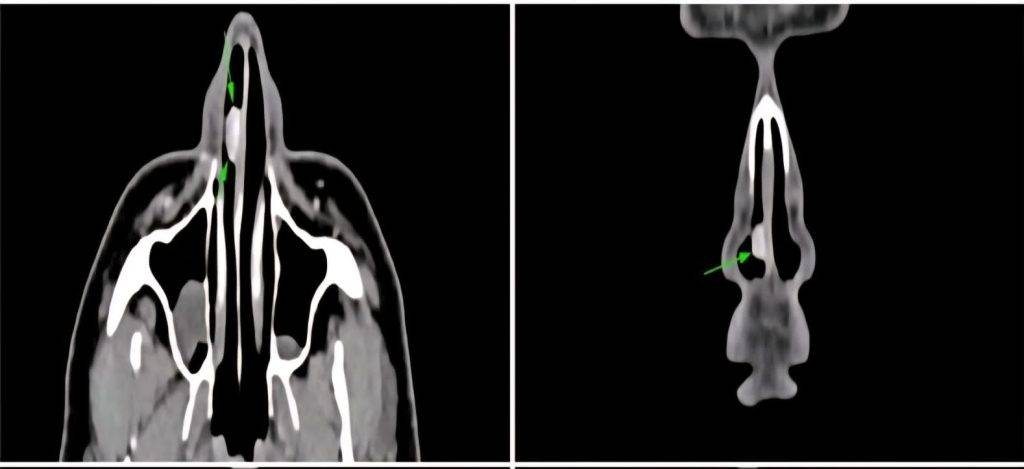

ડૉ. ઠક્કર જણાવે છે કે, નાકની એન્ડોસ્કોપિક તપાસ દરમિયાન દર્દીના જમણા નાકમાં નેસલ સેપ્ટમ સાથે જોડાયેલું લાલ, મસા જેવી અસામાન્ય રચના જોવા મળી. ત્યારબાદ કરાયેલા કોન્ટ્રાસ્ટ CT સ્કેનમાં ખબર પડી કે આ રચના રક્તવાહિનીઓના ગૂંચથી બનેલું પોલિપ જેવું લીઝન છે, જે નેસલ સેપ્ટમમાં જોવા મળવું અત્યંત દુર્લભ છે.

સાવધાનીપૂર્વકની એન્ડોસ્કોપિક તપાસ અને કોન્ટ્રાસ્ટ સાથેની CT સ્કેનથી સાચો નિદાન કરવામાં મદદ મળી અને ત્યારબાદ ટ્યૂમરને સંપૂર્ણપણે દૂર કરવામાં આવ્યો. બાયોપ્સીમાં તેને Anastomosing Hemangioma તરીકે પુષ્ટિ મળી – જે બિન-કૅન્સરજન્ય પરંતુ અત્યંત રેર વાસ્ક્યુલર લીઝન છે.